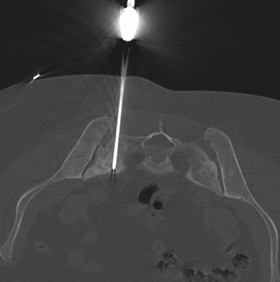

Sacral Bone Biopsy - Narayana Imaging & Diagnostics